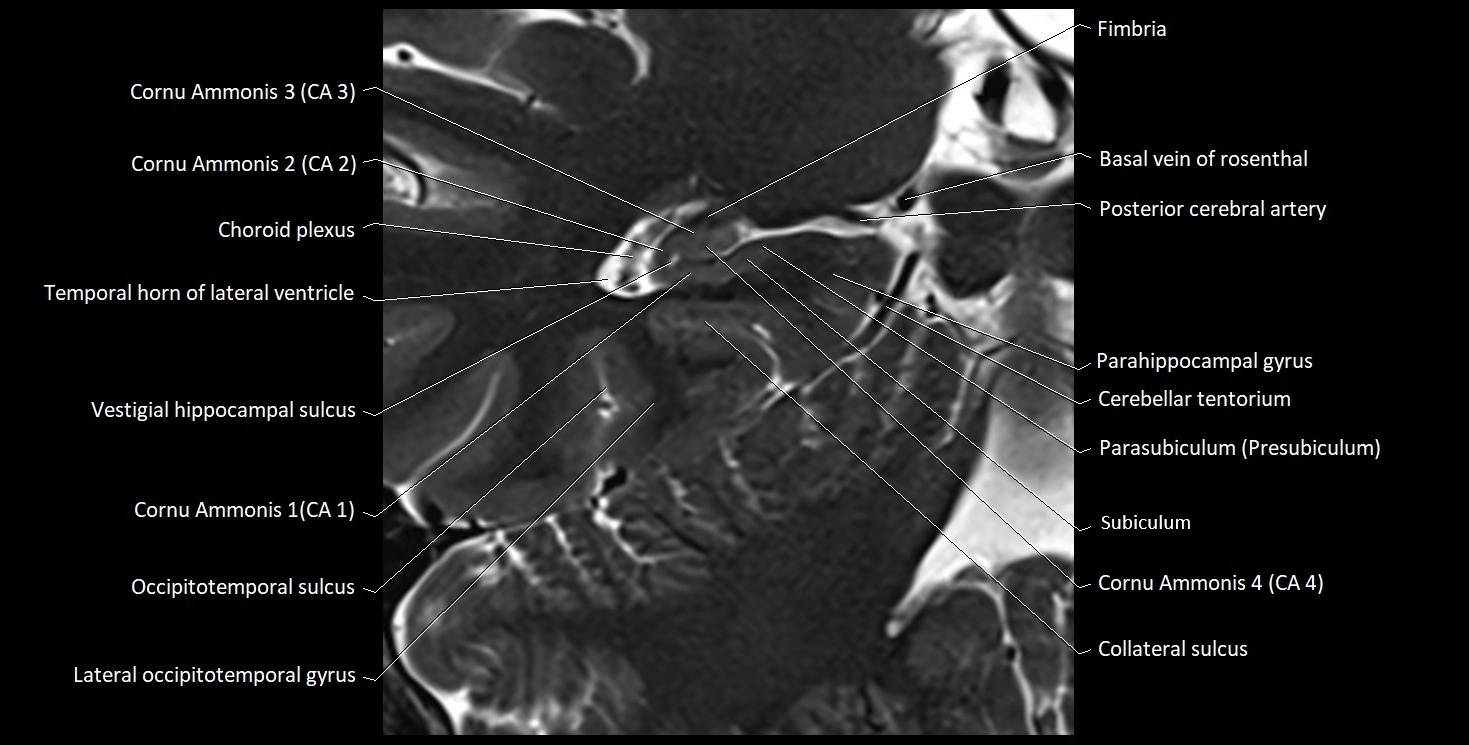

The alveus of the hippocampus is a thin, white matter layer covering the superior (ventricular) surface of the hippocampus within the temporal horn of the lateral ventricle. It consists of myelinated efferent fibers arising primarily from the pyramidal neurons of the hippocampus. These fibers converge medially to form the fimbria of the hippocampus, which continues posteriorly into the fornix, forming a crucial part of the Papez circuit involved in memory consolidation and emotional processing.

The alveus serves as the initial output pathway of the hippocampal formation, linking it to other limbic structures including the hypothalamus, mammillary bodies, and cingulate gyrus. Because of its intimate relationship with the hippocampal head and tail, it is often evaluated in cases of temporal lobe epilepsy, hippocampal sclerosis, and neurodegenerative diseases.

Location and Structure

• Position: Lies on the ventricular (superior) surface of the hippocampus, beneath the ependyma of the inferior horn of the lateral ventricle.

• Composition: A thin sheet of myelinated axons derived mainly from hippocampal pyramidal cells.

• Course: Fibers run medially along the hippocampal surface to form the fimbria of the hippocampus, which curves upward and backward into the fornix.

• Relations:

• Superiorly: Ependyma and CSF of the temporal horn of the lateral ventricle

• Inferiorly: Pyramidal cell layer of the hippocampus (CA1 region)

• Medially: Fimbria and fornix

• Laterally: Temporal lobe white matter and parahippocampal gyrus

MRI Appearance

T1-weighted images:

• Alveus: Thin linear high signal band (due to myelinated fibers) overlying the hippocampal gray matter.

• Hippocampal gray matter: Intermediate signal intensity.

• CSF of lateral ventricle: Dark (low signal).

T2-weighted images:

• Alveus: Low signal line overlying brighter hippocampal gray matter.

• CSF: Bright hyperintense.

MRI images

image